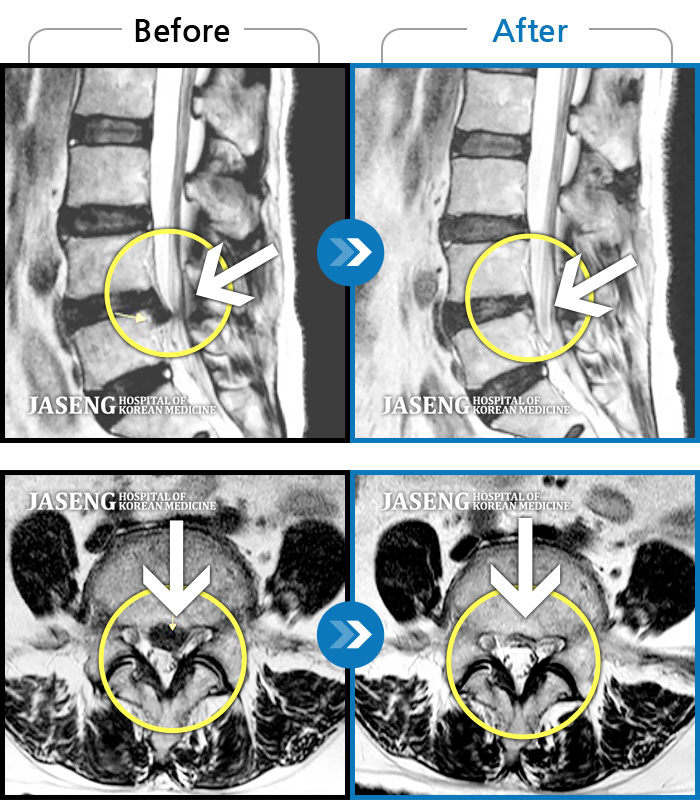

목디스크

많이 본 사례

강남 · 안용준 원장

목부터 좌측 어깨까지 통증이 심해요

촬영시기

2022.07.04 ~ 2024.09.02

2024.12.24

조회수 698